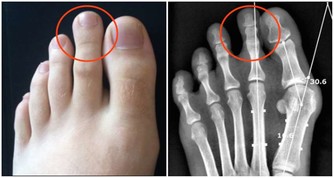

4. 擁有“癌症基因”意味著你注定要患癌症

即使你的直系親屬中有人患過癌症,即使你身上已經出現基因突變,也不是無法避開癌症的。我們的新陳代謝和細胞中有許多錯綜複雜的途徑,其中一些途徑可以打開基因,有些可以將它們關閉。這是一個叫做“表觀遺傳學”的領域,環境和外部影響可以改變基因表達。於是,這使得患者有能力做一些事情,比如吃健康的飲食和鍛煉,這可能會影響最終結果。